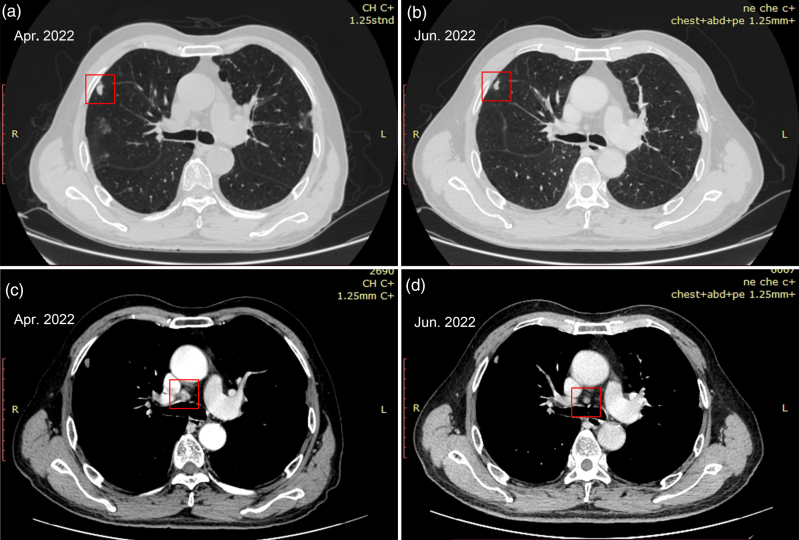

伴有SMARCA4缺陷的非小细胞肺癌(NSCLC)是一种罕见的肺肿瘤亚群,其特点是早期转移、化疗反应差、预后不良。对于缺乏smarca4的NSCLC,已建立的治疗策略仍然难以捉摸。虽然免疫检查点抑制剂已被提出作为一种潜在的解决方案,但其功效仍不确定。临床因素如肿瘤突变负担(TMB)、微卫星不稳定性、计算和程序性死亡配体1 (PD-L1)表达可能影响smarca4缺陷NSCLC的治疗反应。此外,循环肿瘤细胞(CTCs)上的PD-L1表达为监测提供了新的见解,其在smarca4缺陷NSCLC中的应用仍未被探索。本报告描述了一例71岁男性被诊断为缺乏smarca4的非小细胞肺癌,他有大量吸烟和慢性咳嗽的历史。影像学检查显示淋巴结转移。血清肿瘤标志物均高于正常范围。右上肺原发性病变活检标本的组织病理学和免疫组织化学分析显示肿瘤细胞排列不规则,SMARCA4缺乏,PD-L1阳性表达。进一步的下一代测序证实了SMARCA4突变,高TMB和微卫星稳定性(MSS)。患者接受了派姆单抗治疗,并经历了持续40个月的持续获益,在整个治疗过程中观察到ctc上持续的PD-L1表达。研究显示,派姆单抗治疗对具有PD-L1阳性表达、高TMB和MSS的smarca4缺陷NSCLC患者显示出希望。动态监测CTCs上的PD-L1状态可能有助于评估免疫治疗反应,CTCs上持续的PD-L1阳性表达可能意味着smarca4缺陷NSCLC患者从免疫治疗中持续获益。

Nonsmall cell lung cancer (NSCLC) with SMARCA4 deficiency represents a rare subset of lung tumors characterized by early metastasis, poor response to chemotherapy, and unfavorable prognosis. Established therapy strategies for SMARCA4-deficient NSCLC remain elusive. While immune checkpoint inhibitors have been proposed as a potential solution, their efficacy remains uncertain. Clinical factors such as tumor mutational burden (TMB), microsatellite instability, comutations, and programmed death-ligand 1 (PD-L1) expression may influence the treatment response of SMARCA4-deficient NSCLC. Additionally, PD-L1 expression on circulating tumor cells (CTCs) provides novel insights for monitoring, and its utility in SMARCA4-deficient NSCLC remains unexplored. The present report describes the case of a 71-year-old man diagnosed with SMARCA4-deficient NSCLC who had a history of heavy smoking and chronic cough. Imaging examination revealed metastatic lymph nodes. All serum tumor markers were elevated above the normal range. Histopathological and immunohistochemical analyses of the biopsy specimen from a primary lesion in the right upper lung demonstrated irregularly arranged tumor cells, SMARCA4 deficiency, and positive PD-L1 expression. Further next-generation sequencing confirmed SMARCA4 mutation, high TMB, and microsatellite stability (MSS). The patient received pembrolizumab treatment and experienced a sustained benefit for >40 months, with persistent PD-L1 expression on CTCs observed throughout the treatment. It was revealed that pembrolizumab therapy shows promise for patients with SMARCA4-deficient NSCLC with positive PD-L1 expression, high TMB, and MSS. Dynamic monitoring of PD-L1 status on CTCs may facilitate the assessment of the immunotherapy response, and the sustained positive PD-L1 expression on CTCs may imply continued benefit from immunotherapy for patients with SMARCA4-deficient NSCLC.